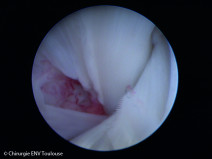

• Formation pratique en arthroscopie niveau 1

Formation complète

La simulation sous toutes ses formes permet d’apprendre et de répéter les gestes ou les actions dans des conditions proches du réel et sans le stress émotionnel.

L’école de Chirurgie de Nancy qui possède un plateau technique dédié d'exception ouvre ses portes aux formations pratiques vétérinaires. L'intervenant, le Dr Jean-Guillaume Gr...